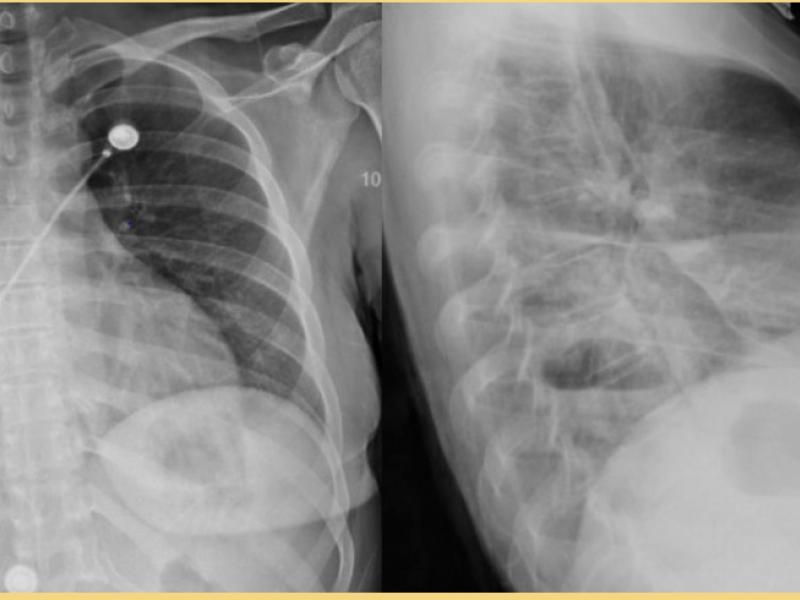

What's the diagnosis?  By Dr. Becca Fieles

December 23 2020

A 30 yo female with a hx of IVDA presents with 2 weeks of